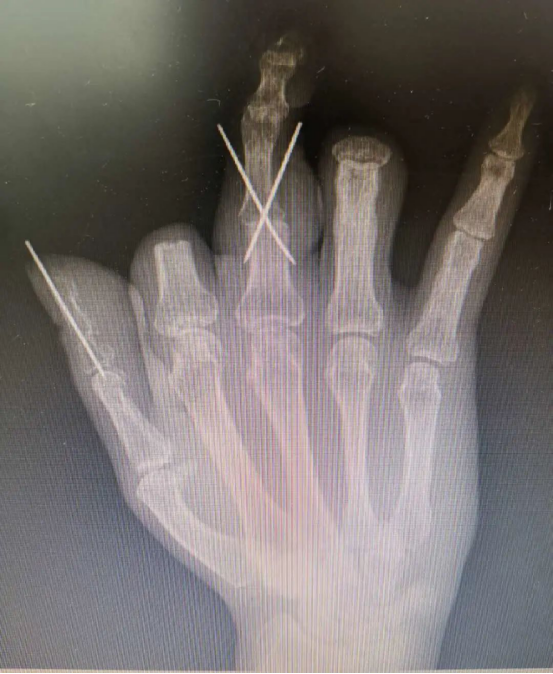

手術過程順利,由于3D打印技術的精準化輔助,兩根再造的手指外形美觀,不需要進行二期整形修復,足部供區(qū)創(chuàng)傷也達到最小化。又能用右手寫字、吃飯,陳先生很高興,“等這兩根手指恢復得差不多了,我馬上就來修復剩下兩根手指!”